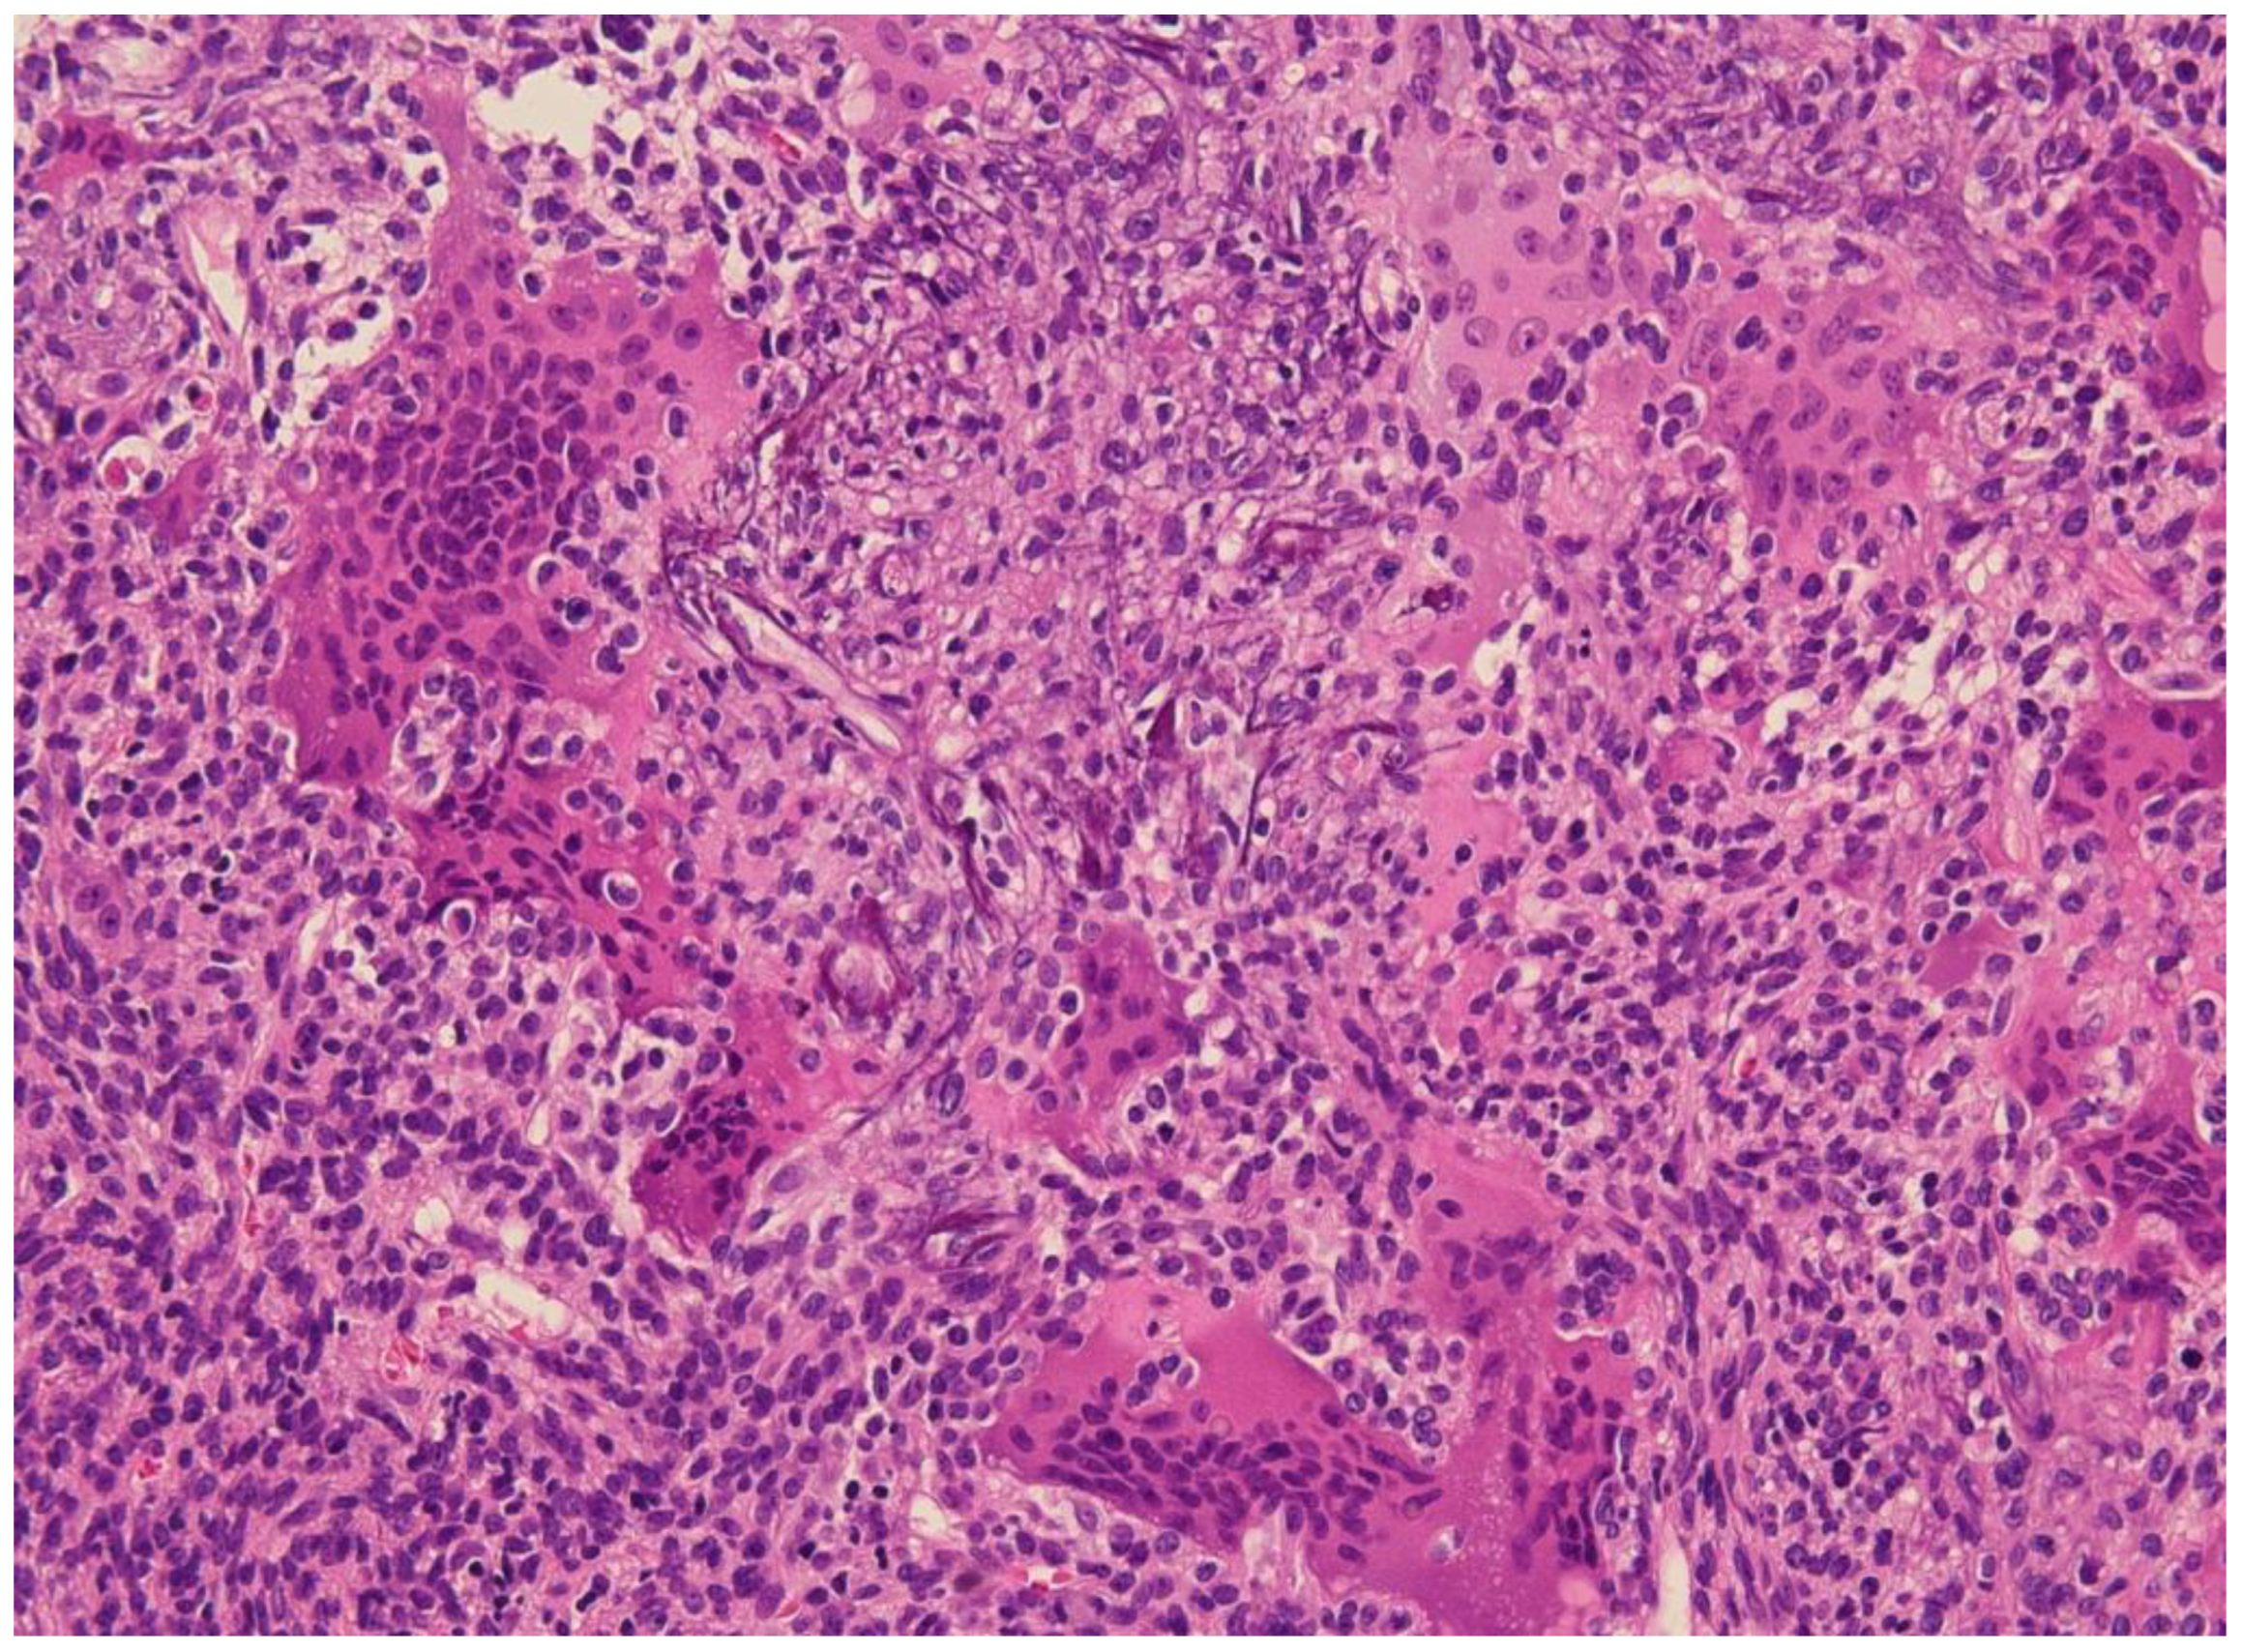

4. Surgery and Non-Surgical Alternatives